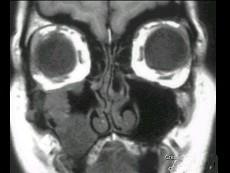

问题 女性,50岁,右鼻塞、脓涕3个月,CT、MRI检查如图所示,请选择正确的答案 ( )

选项 A、右侧上颌窦黏液腺瘤 B、右侧上颌窦腺样囊性癌 C、右侧上颌窦粘膜下囊肿 D、右侧上颌窦积液 E、右侧上颌窦黏液囊肿

答案 B